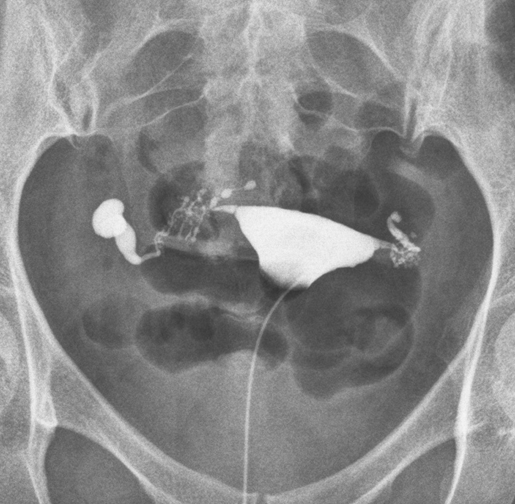

其实,峡部结节性输卵管炎的子宫输卵管造影表现很典型,表现为输卵管峡部周围多个造影剂聚集的小囊状憩室, 憩室与输卵管主管腔相通, 憩室直径大小多在0.1-2mm,丛集在长约2厘米输卵管峡部周围,相邻的输卵管间质部有时会累及(图1)。看到就会记住,只要心中有这个概念,就不会诊断错误。峡部结节性输卵管炎一经诊断,只要经济条件可以,就应该直接试管婴儿。

1.png

图1 峡部结节性输卵管炎典型造影表现